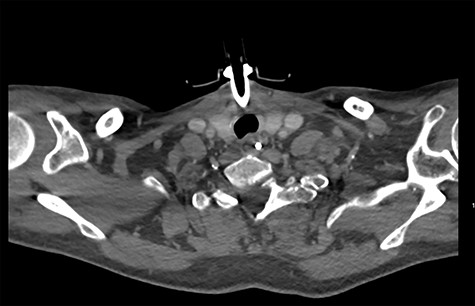

On diagnosing the right VCP, the original trauma series was reviewed by a consultant radiologist who identified a haematoma of the right carotid sheath in the neck (Fig. 1). A second CT scan of the neck and thorax was performed to determine the cause of the VCP 20 days after admission. This did not show a cause for the VCP but did demonstrate resolution of the haematoma (Fig. 2). A second FNE demonstrated resolution of the VCP 29 days following admission.

CT showing haematoma in the right carotid sheath following insertion of central line.